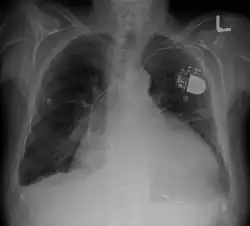

- Chest X-ray: X-ray images help to visualize the condition of the lungs and heart. If the heart is enlarged on an X-ray, other tests will usually be needed to find the cause. A useful measurement on X-ray is the cardio-thoracic ratio, which is the transverse diameter of the heart, compared with that of the thoracic cage.[30] These diameters are taken from PA chest x-rays using the widest point of the chest and measuring as far as the lung pleura, rather than lateral skin margins. If the ratio is greater than 50%, pathology is suspected.[31] The measurement was first proposed in 1919 to screen military recruits. A newer approach to using these x-rays for evaluating heart health takes the ratio of heart area to chest area and has been called the two-dimensional cardiothoracic ratio.[32]

Devices to regulate heartbeat

- Pacemaker: Coordinates contractions between ventricles. In people at risk of arrhythmias, drug therapy or an implantable cardioverter-defibrillator (ICD).

- ICDs: Small devices implanted in the chest to monitor heart rhythm and deliver electrical shocks to control abnormal heartbeats. The devices can also work as pacemakers.